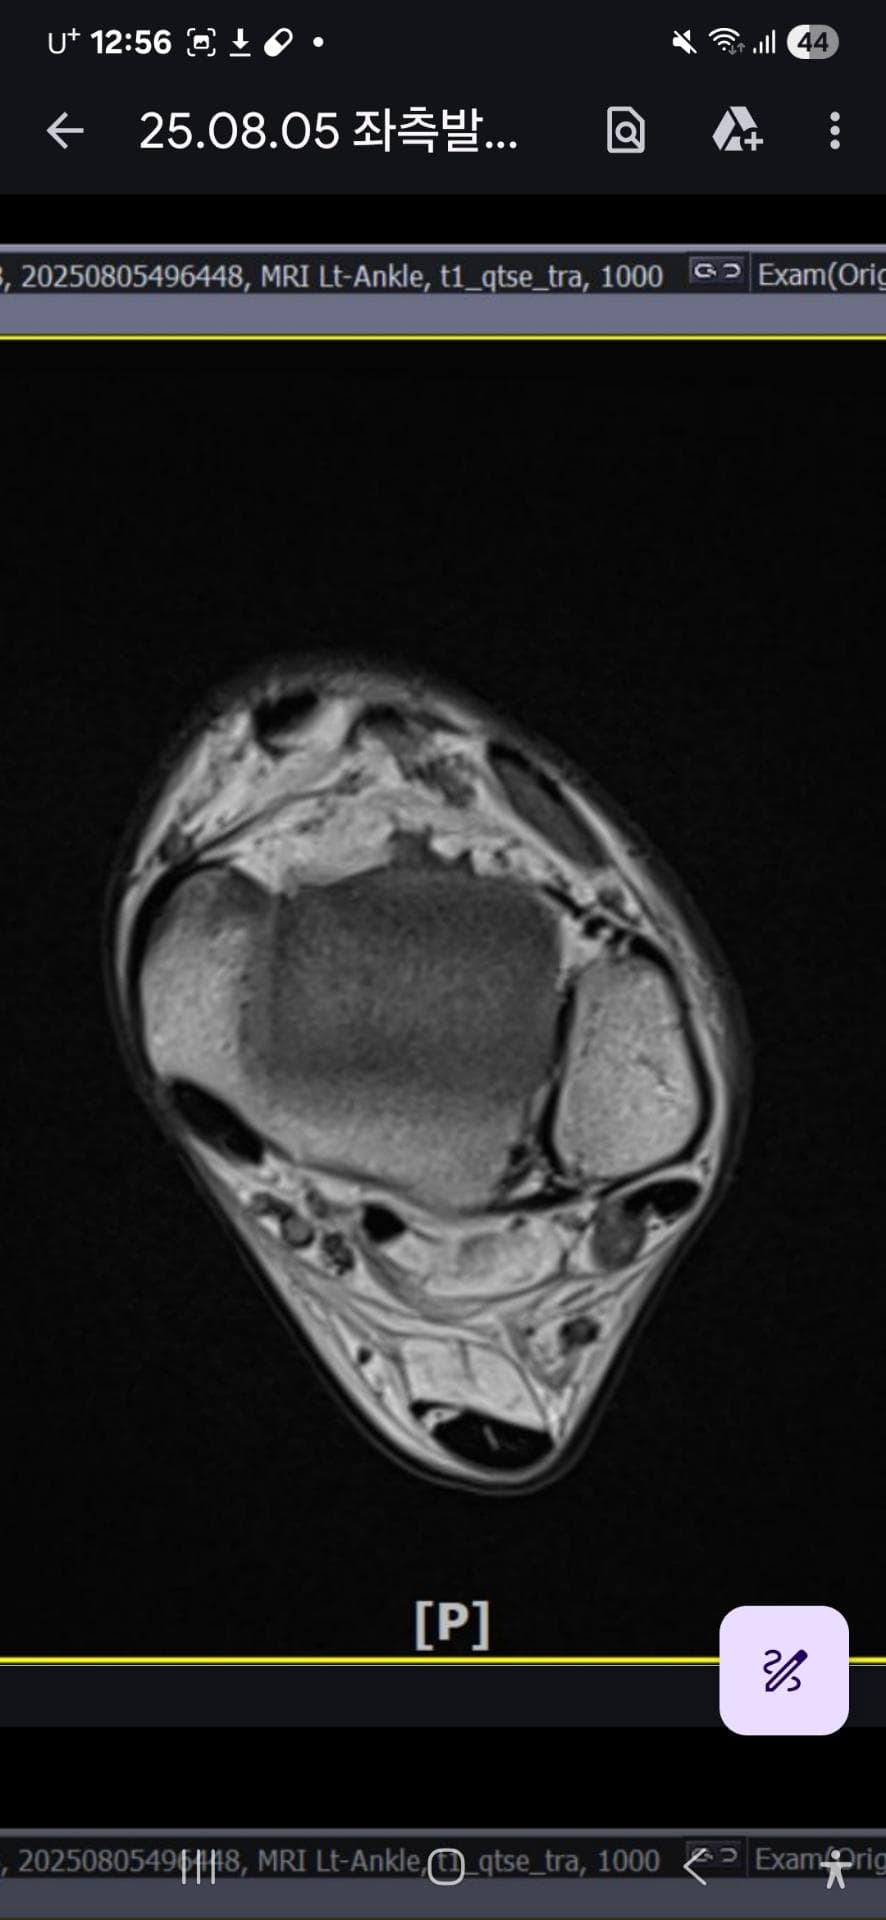

그래도 통증이 남아 8월 5일에 MRI를 촬영했는데, 병원에서는 “인대는 이어져 있고, 이 정도면 재활운동으로 호전될 것”이라는 설명을 들었습니다.

MRI 상 전거비인대와 발목 상태가 정말 회복 단계인지, 아니면 만성으로 넘어가는 건 아닌지 전문가분들의

의견을 듣고 싶습니다.

올려주신 mri를 보면 전거비인대는 연속성이 유지되고 있고 파열이나 큰 손상 흔적은 없어 재활로 회복 가능한 상태로 보입니다 다만 3개월 가까이 활동 시 통증과 미열감이 남아 있는 것은 조직 회복이 아직 완전히 끝나지 않았거나 주변 연부조직 관절 움직임 제한 등으로 인한 과민 반응일 수 있습니다.

초음파와 비교하면 mri 상으로 인대 연속성이 확인되므로 심각한 악화나 재파열은 아닌 것으로 판단됩니다